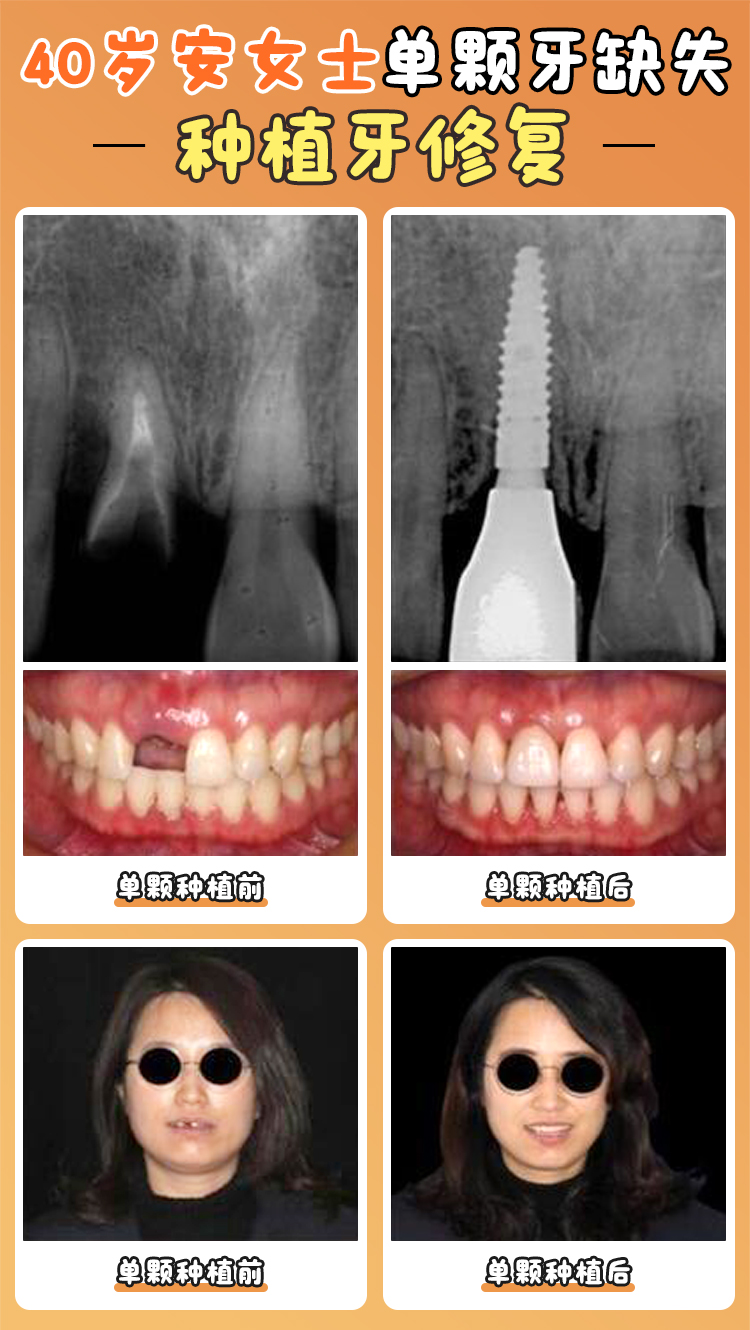

滬申口腔醫(yī)院做種植牙怎么樣呢?答案是相當(dāng)不錯(cuò)!這里技術(shù)多樣,收費(fèi)合理,還有貼心的服務(wù)和經(jīng)驗(yàn)多的醫(yī)生團(tuán)隊(duì),下面就為大家詳細(xì)介紹。m.sorencai.cn

滬申口腔醫(yī)院擁有一支經(jīng)驗(yàn)多的醫(yī)生團(tuán)隊(duì)。熊懸峰是口腔科種植技術(shù)總監(jiān)、副高醫(yī)師,還是韓國(guó)奧齒泰種植系統(tǒng)認(rèn)證醫(yī)師、瑞典諾貝爾種植系統(tǒng)認(rèn)證講師。他擅長(zhǎng)即刻種植牙、上頜竇提升術(shù)、單顆/多顆/半口/全口種植、高難度all - on - 4/6種植、骨增量技術(shù),完成種植超5000例,還能處理外院轉(zhuǎn)診疑難病例。

汪龍河是種植院長(zhǎng),深耕種植領(lǐng)域18年以上,累計(jì)完成種植手術(shù)超5000例,種牙患者回訪滿意度達(dá)98%。他擅長(zhǎng)數(shù)字化微創(chuàng)口腔種植、半口/全口種植、上頜竇內(nèi)/外提升、穿翼板種植技術(shù)、ALL - ON - 4/6即刻拔牙/種植/修復(fù)、骨增量、全口咬合重建,10年植體存活率達(dá)95%以上。

夏薇是副高醫(yī)師,有20余年臨床經(jīng)驗(yàn),多次赴德/美/俄等國(guó)研修種植與正畸。她擅長(zhǎng)美學(xué)種植牙修復(fù)、咬合重建、美學(xué)正畸、前牙區(qū)“紅白美學(xué)”重建,精通種植與正畸聯(lián)合治療。86~#82.cc